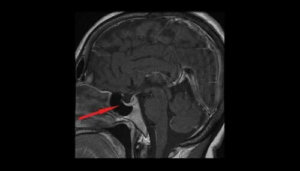

Tanıyı doğrulamaya yardımcı olan en doğru testler görme alanı testleri ve CT ile beyin emarıdır.(MRI)